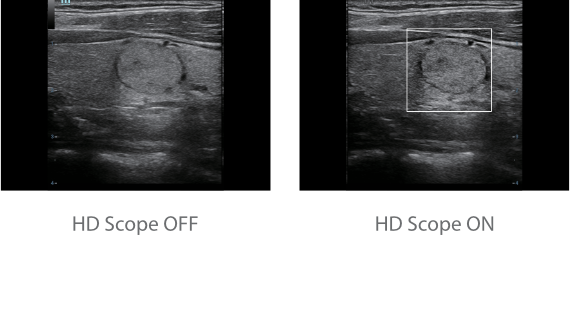

?? Resona 7? ???? ??? ?? ???? ??? ??? ???? ??? ?? ???? V Flow? ?? CNS ??? ?? 3D ??? ???? ?? ???? ?? ??? ?? ?? ?? ??? ??????. ???? ??? ??? ?? ?? ??? ??? ?? ?? ??? ??? Resona 7? ??? ???? ???? ??? ??? ??? ????.